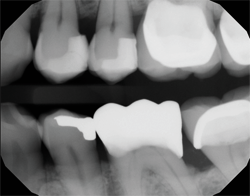

A recent example shows how a CariVu image can provide peace of mind to even the most doubting people. A patient arrived at my office with the problem of sensitivity on chewing. He told me that he did not think that the tooth was cracked. As a science education teacher at a local college, he felt confident in his self-diagnosis, and narrowed his problem down to one of two teeth. CariVu images showed him that in actuality, both teeth had cracks. The first CariVu image shows a crack on the mesial of tooth #3 (Fig. 4), and the second image shows cracks on the distal of tooth #3 and on the mesial of tooth #2 (Fig. 5). Of note is the dark area around the crack on #2 that represents the spreading caries that originate from the fracture. When faced with the evidence on the CariVu images, this skeptical science person now understood where his sensitivity was originating from, and he was eager to make the appointment for the appropriate repairs to those teeth.